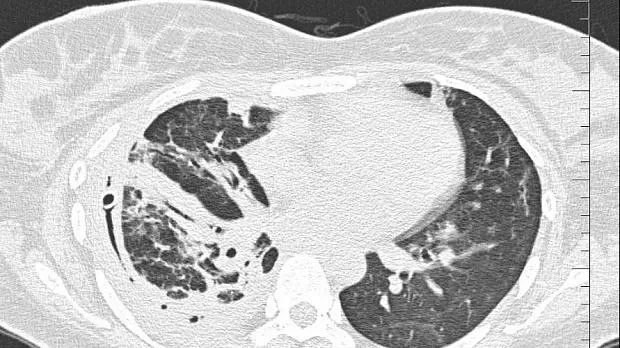

08.06.2020 проведена повторная установка блокатора в промежуточный бронх (блокатор Medlung №13) с хорошим клиническим эффектом (сброс воздуха по плевральному дренажу прекратился через 8 часов после вмешательства). Подтверждено данными Р-КТ органов грудной клетки.